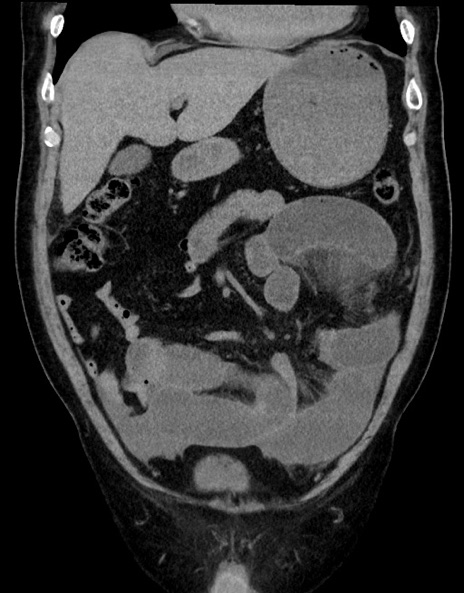

症例15(冠状断像)

【症例】70歳代男性

【主訴】腹痛

【現病歴】今朝から腹痛あり。全体的に痛い。特に左上の方。排ガスが今日はない。冷や汗が出る。

【既往歴】直腸癌術後

【身体所見】左側腹部〜上腹部に圧痛あり。腹膜刺激症状明らかなではない。軽度反跳痛。左下腹部に術後瘢痕あり。

【データ】WBC 7700、CRP 0.02